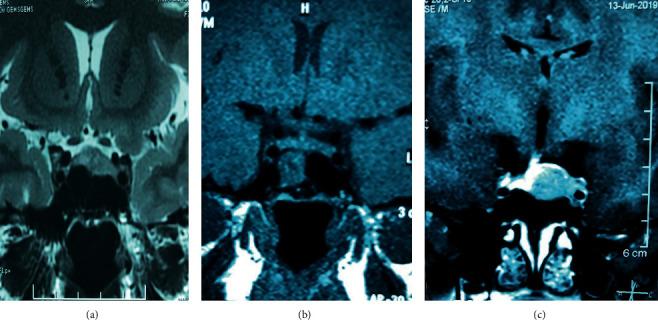

INTRODUCTION

Synchronous bilateral adrenalectomy is undertaken less often due to numerous perioperative challenges and rare circumstances of patients needing this procedure. Bilateral adrenalectomy is an important second-line option for patients with persistent or recurrent hypercortisolism following transsphenoidal surgery for Cushing's disease. Here, we present a challenging case of synchronous laparoscopic bilateral adrenalectomy for a young female patient with recurrent Cushing's disease and fertility wishes. . A 21-year-old recently married patient who was diagnosed with Cushing's disease with a pituitary microadenoma had undergone two attempts of transsphenoidal excision of the pituitary tumour. Follow-up evaluation showed an unresectable residual tumour with invasion of the intracavernous part of the left internal carotid artery. As the patient had the hypothalamic-pituitary-ovarian axis intact with strong fertility wishes, she was offered bilateral adrenalectomy instead of radiotherapy. She was prepared for the surgery with close perioperative support from the endocrinology and anaesthesia teams. Intravenous hydrocortisone infusion was started at the induction of anaesthesia. Transperitoneal approach was used with the patient positioned in left and right lateral positions for right and left glands, respectively. A meticulous surgical technique was used for the identification of adrenal veins to clip them before division followed by handling of the glands. The patient had minimal haemodynamic disturbances during surgery. Intraoperative blood loss was less than 100 ml, and operative time was 220 minutes. She had a gradual recovery following postoperative respiratory distress due to basal atelectasis and consolidation. Cortisol levels were less than 20 nmol/L postoperatively, suggesting successful surgical intervention. Two months after surgery, she continued on maintenance therapy of oral hydrocortisone and fludrocortisone and was encouraged to go ahead with pregnancy.

由于围手术期存在诸多挑战且需要进行该手术的患者情况罕见,同期双侧肾上腺切除术的开展频率较低。对于库欣病经蝶窦手术后仍持续或复发高皮质醇血症的患者,双侧肾上腺切除术是一项重要的二线选择。在此,我们报告一例具有挑战性的病例,为一名有生育意愿的年轻女性复发性库欣病患者进行同期腹腔镜双侧肾上腺切除术。一名21岁近期结婚的患者,被诊断为患有垂体微腺瘤的库欣病,已接受过两次经蝶窦垂体肿瘤切除术。随访评估显示存在不可切除的残留肿瘤,且肿瘤侵犯了左颈内动脉海绵窦段。由于患者下丘脑 - 垂体 - 卵巢轴完整且有强烈的生育意愿,因此为其提供了双侧肾上腺切除术而非放射治疗。在内分泌科和麻醉科团队的密切围手术期支持下,她为手术做好了准备。麻醉诱导时开始静脉输注氢化可的松。采用经腹途径,患者分别取左侧和右侧卧位以切除右侧和左侧肾上腺。手术中采用精细的技术识别肾上腺静脉,在离断前进行夹闭,随后处理肾上腺。患者手术过程中血流动力学干扰极小。术中失血少于100毫升,手术时间为220分钟。术后因基底肺不张和实变出现呼吸窘迫,之后逐渐康复。术后皮质醇水平低于20纳摩尔/升,表明手术干预成功。术后两个月,她继续接受口服氢化可的松和氟氢可的松的维持治疗,并被鼓励继续妊娠。